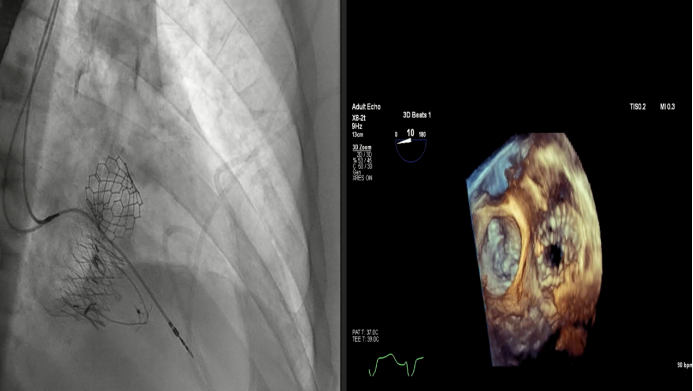

2023年美國心血管研究技術(shù)年度研討會(CRT)在美國華盛頓舉行。作為全球心臟瓣膜介入治療領(lǐng)域的頂級盛會之一,CRT吸引著來自全球瓣膜領(lǐng)域?qū)<覍W者的目光。在本次大會上,來自法國CHU de Bordeaux的Thomas Modine教授和來自美國Henry Ford Hospital的Dee Dee Wang教授分別報告了關(guān)于通過頸內(nèi)靜脈放置Lux-Valve Plus的早期數(shù)據(jù)和Lux-Valve Plus術(shù)中的超聲指引經(jīng)驗。

Dee Dee Wang教授分享了Henry Ford Hospital前4例Lux-Valve Plus的植入經(jīng)驗,并提示術(shù)中確定瓣葉夾持鍵的位置處于三尖瓣瓣環(huán)下方(右心室側(cè)),以及室間隔固定片與室間隔的相對位置關(guān)系是最關(guān)鍵的兩個步驟。使用經(jīng)胃底短軸切面,有時配合右室流入/流出道切面的X-plane就能較容易地獲取相關(guān)影像。由于Lux-Valve Plus對超聲影像的要求較低,手術(shù)過程會相對比較流暢。